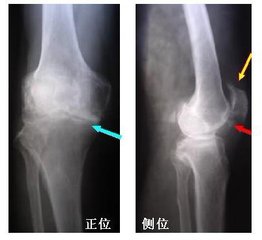

膝骨关节炎术后关节肿痛原因及改善方法揭秘膝关节的一种微创的检查和治疗方法,主要是在膝关节表面做一个或多个开放性小口,通过小口将微创的设备放入关节内,完成膝关节基本病变的检查。 包括膝关节内紊乱(半月板损伤、游离体、滑膜嵌入),关节内不明原因的肿痛、滑膜炎症(类风湿、痛风、结核、滑膜炎等),关节软骨损伤及...